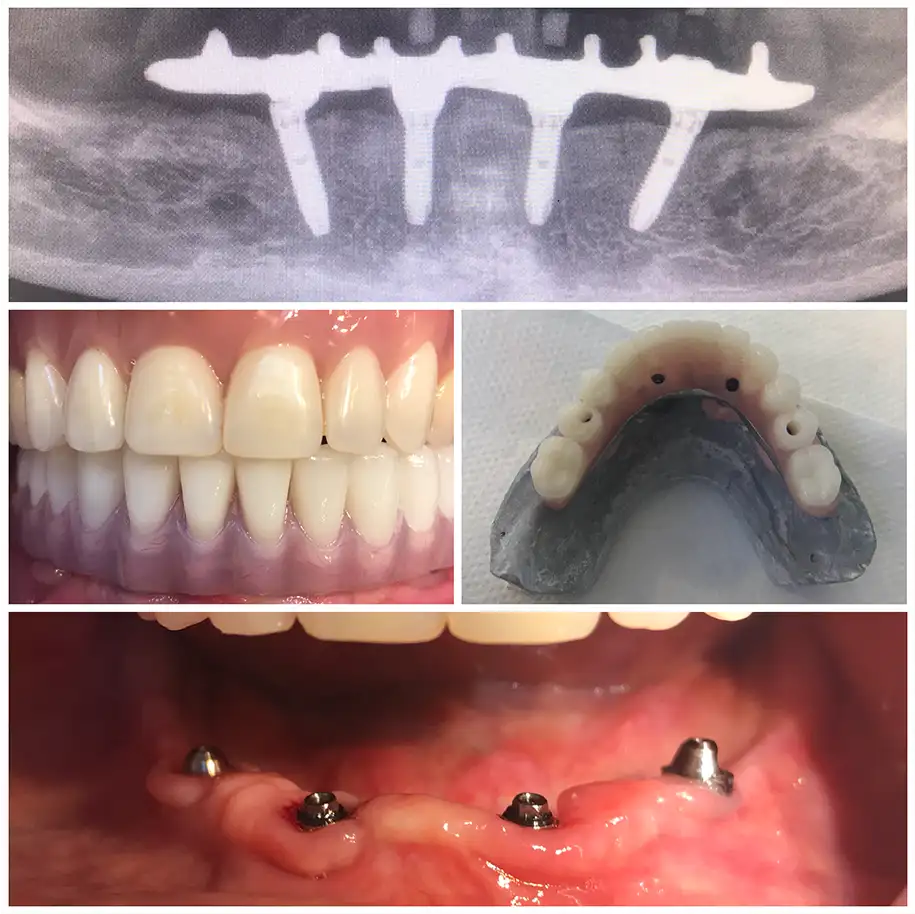

ZAHNMEDIZIN VORHER NACHHER